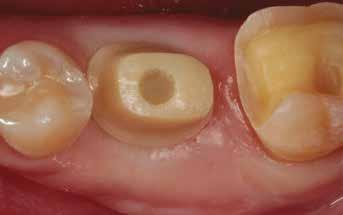

A behelyeztt implantátum primer stabilitását megfelelőnek ítéltük (kb. 40 Ncm) az azonnali terheléshez (9. kép).

Az extrakciót megelőző szituációs lenyomat alapján gyári, titán, ideiglenes abutment felhasználásával, a szék mellett készített, csavaros rögzítésű, azonnali akrilát ideiglenes koronával láttuk el, melyet 20 Ncm nyomatékkal rögzítettünk (10. kép). Az azonnali terhelés szabályainak megfelelően, az ideiglenes korona nem volt kontaktusban a szomszédos és az antagonista fogakkal.

6. kép: Implantátum-ágy preparáció. 7. a–b. képek: Implantátum behelyezés. 8. kép: A behelyezett implantátum. 10. a–b képek: Azonnali ideiglenes korona készítése. 9. kép: Megfelelő primer stabilitás.

A 2020 januárjában elkezdett kezeléssorozat befejezését az év márciusában, hazánkba is begyűrűző Covid-19 pandémia késleltette, így kb. 6 hónap gyógyulás után láttunk hozzá az emergencia profil és a gingivális zenit ideiglenes koronával történő formázásához (11. és 12. kép). A 3 hetente végzett apró alakításokkal sikerült megfelelő ínyprofilt kialakítani, a „rózsaszín esztétika” a páciens számára is megfelelő volt. A bal felső nagymetsző fog meziális kompozit tömés cseréjét követően, individualizált nyitott kanalas lenyomati fejet készítettünk: az akrilát ideiglenes korona profilját átlátszó szilikonnal lemásoltuk, majd a körszimmetrikus gyári lenyomati fej és az ideiglenes korona kontúrja közötti hézagot folyékony kompozittal töltöttük ki (13. kép). Az így készített egyéni lenyomati fejjel vettünk lenyomatot a végleges, kerámialeplezésű cirkónium-dioxid vázas, átmenő csavaros rögzítésű koronához. (A fogtechnikai munkát Nébl Péter fogtechnikusmester készítette.), (14., 15., 16 és 17. képek).